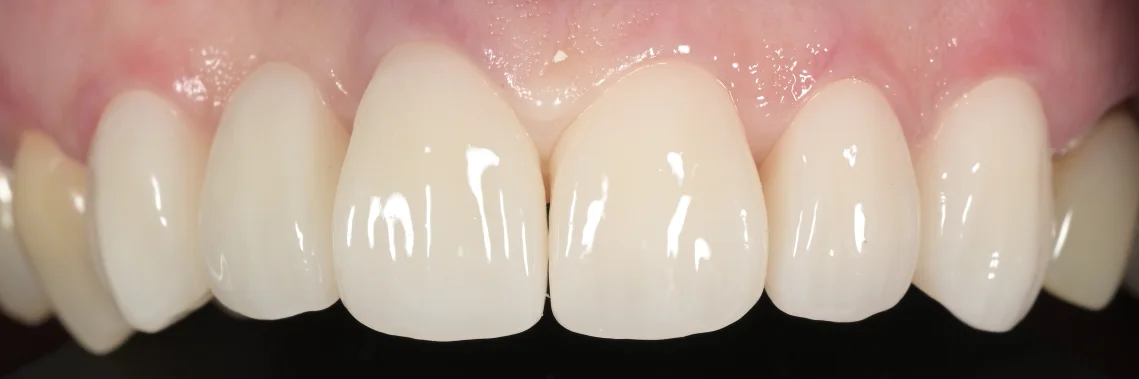

最終的なものがこちらです。

噛む面から撮影したものがこちらになります。